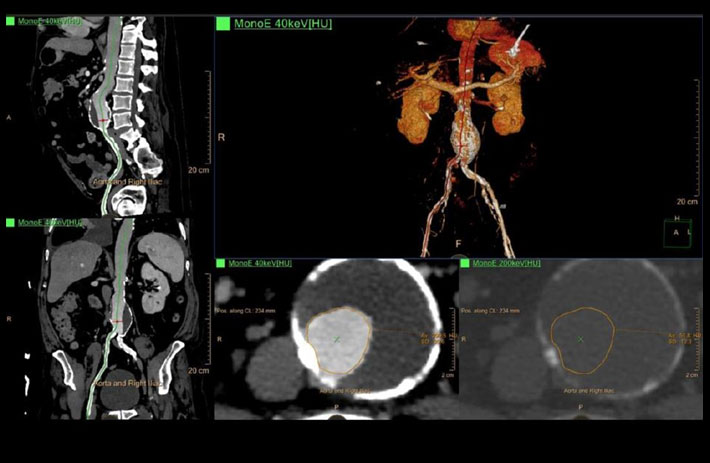

Mit dem Spektral-Detektor-CT werden Spektraldaten automatisch bei jedem Scan erfasst. Die Informationen stehen jederzeit auf der Scankonsole, der CT-Workstation sowie an jedem PACS-Arbeitsplatz zur Verfügung, sodass es nicht notwendig ist, den Patienten erneut zu scannen, bspw. wenn initial zufällige Anomalien festgestellt wurden. Dadurch profitieren Anwender durch eine höhere Diagnosesicherheit und weniger Nachuntersuchungen auf anderen bildgebenden Systemen. Unsere Fallsammlung zeigt, welchen klinischen Mehrwert der Spektral-Detektor-CT in unterschiedlichsten Anwendungsbereichen in der klinischen Routine bringt. Jede Woche gehen neue Fälle live.